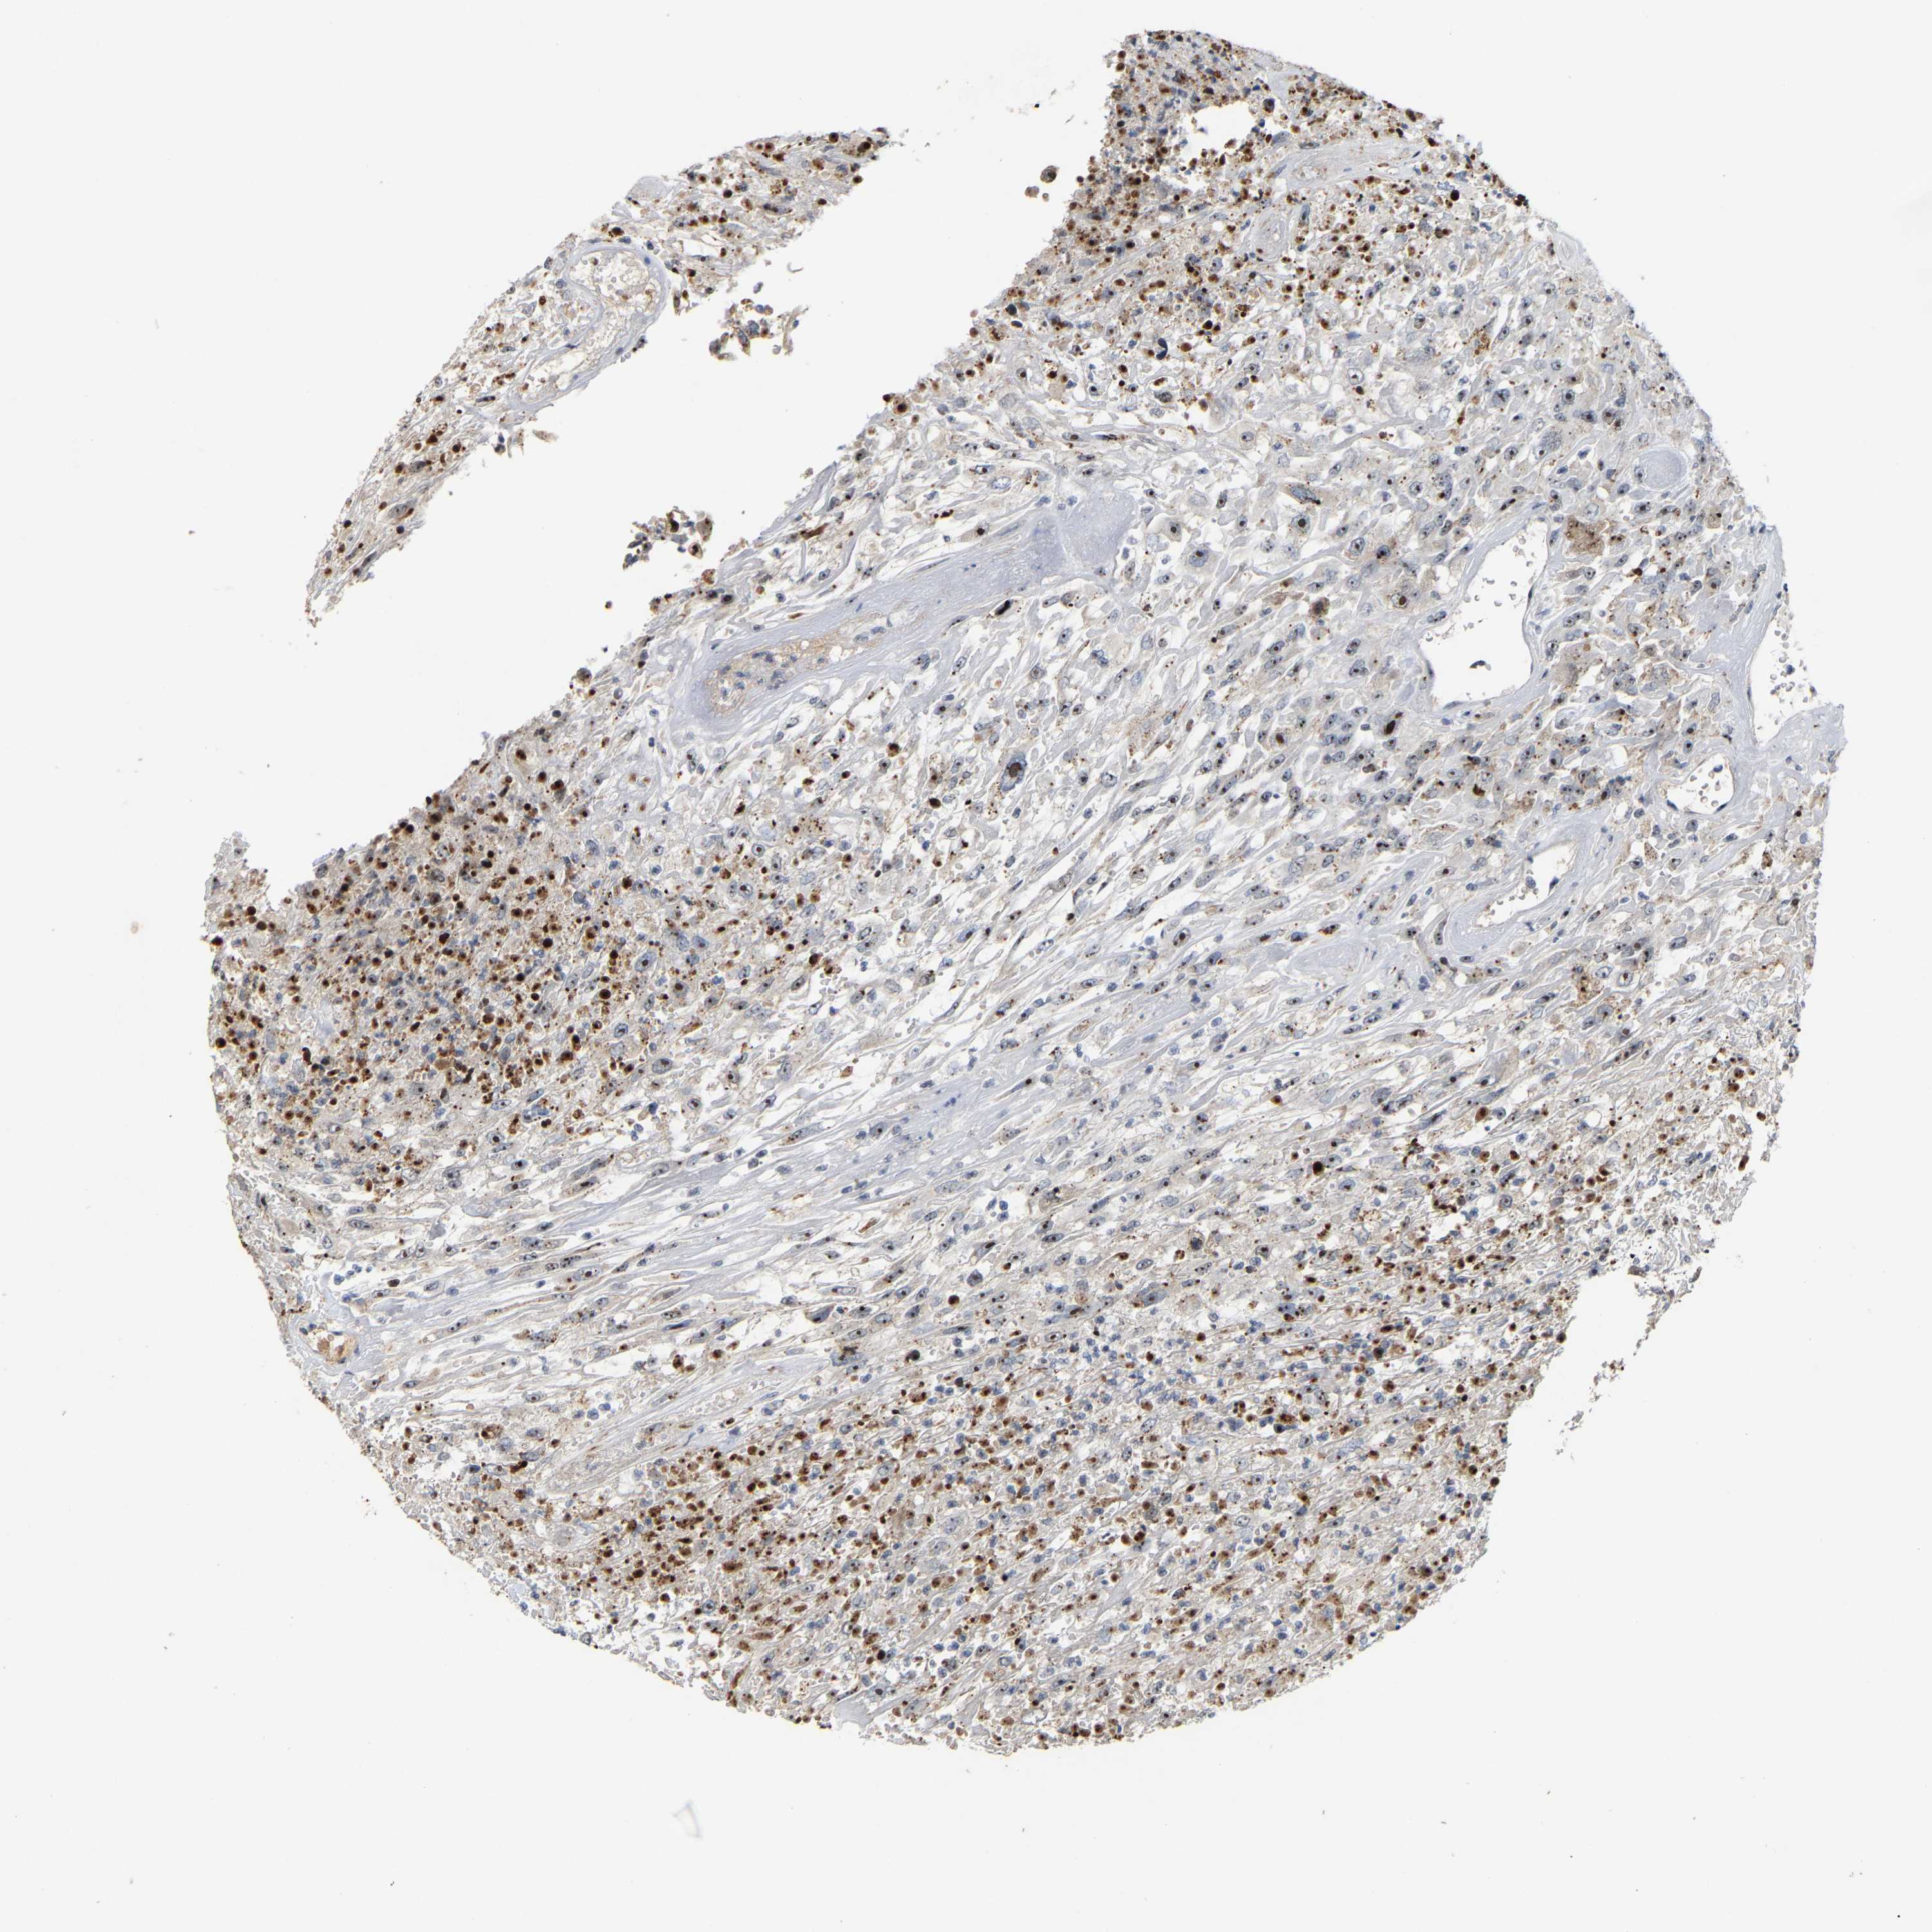

UROTHELIAL CANCER - Protein expressioni

A mouse-over function shows sample information and annotation data. Click on an image to view it in a full screen mode. Samples can be filtered based on level of antibody staining by selecting one or several of the following categories: high, medium, low and not detected. The assay and annotation is described here.

Note that samples used for immunohistochemistry by the Human Protein Atlas do not correspond to samples in the TCGA dataset.

Antibody stainingi

Antibody staining in the annotated cell types in the current human tissue is reported as not detected, low, medium, or high, based on conventional immunohistochemistry profiling in selected tissues. This score is based on the combination of the staining intensity and fraction of stained cells.

Each image is clickable and will lead to virtual microscopy that enables deeper exploration of all samples and also displays staining intensity scores, fraction scores and subcellular localization as well as patient and tissue information for each sample.

Antibody HPA018472

Antibody HPA021062

Urothelial carcinoma, Low grade

Urothelial carcinoma, High grade